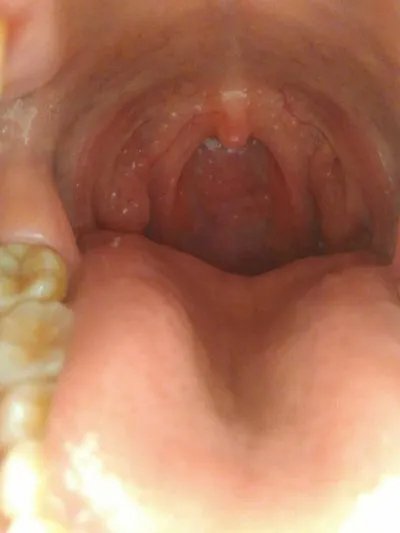

,舌癌的早期症状? 第一、突然出现的唾液分泌增多、流涎、鼻涕带血、吞咽哽噎感、颌面部肿块及淋巴结肿大,并且持续存在,甚至逐渐加重,突然出现的舌头运动受限、语言不清、说话和吞咽时感到疼痛;局限性唇红粘膜增厚与鳞屑形成,伴有灰白色角化斑,

第三、口腔内突然出现粘膜红斑、水肿、糜烂、白斑皲裂、扁平舌藓、隆起和颗粒状肉芽等,主观感觉极其不敏感,但经过治疗2周—4周非但不愈,这些舌癌早期症状反而会慢慢扩散增大。